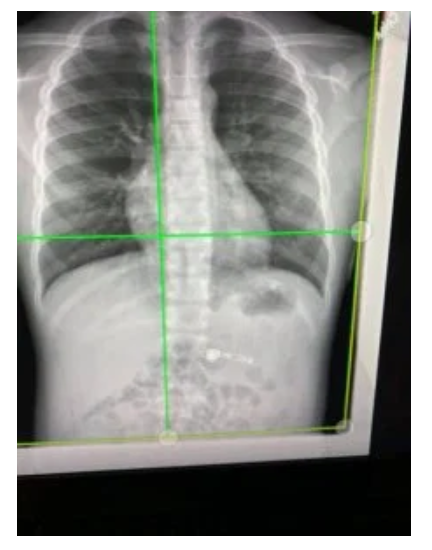

他的母亲Kiara Stroud将他送往急诊室,医生为孩子拍摄了X光片。医生可以看到无线耳机位于他的肋骨下面。

“我们实际上看到了它,因为它里面有金属,所以我们可以在X射线中看到它,我想,'这个男孩真的吞下了他的AirPod!'”Stroud告诉新闻媒体。